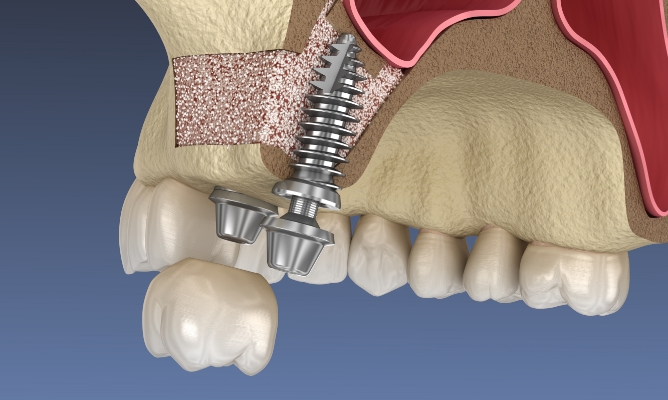

• 3D CT

디지털 CT를 통해 개인의 구강구조를

꼼꼼하고 정확하게 파악 후 치료계획을

수립해 시행착오를 줄입니다.